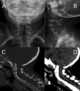

Sprengel's deformity (also known as high scapula or congenital high scapula) is a rare congenital skeletal abnormality where a person has one shoulder blade that sits higher on the back than the other. The deformity is due to a failure in early fetal development where the shoulder fails to descend properly from the neck to its final position. [Source: Wikipedia ]